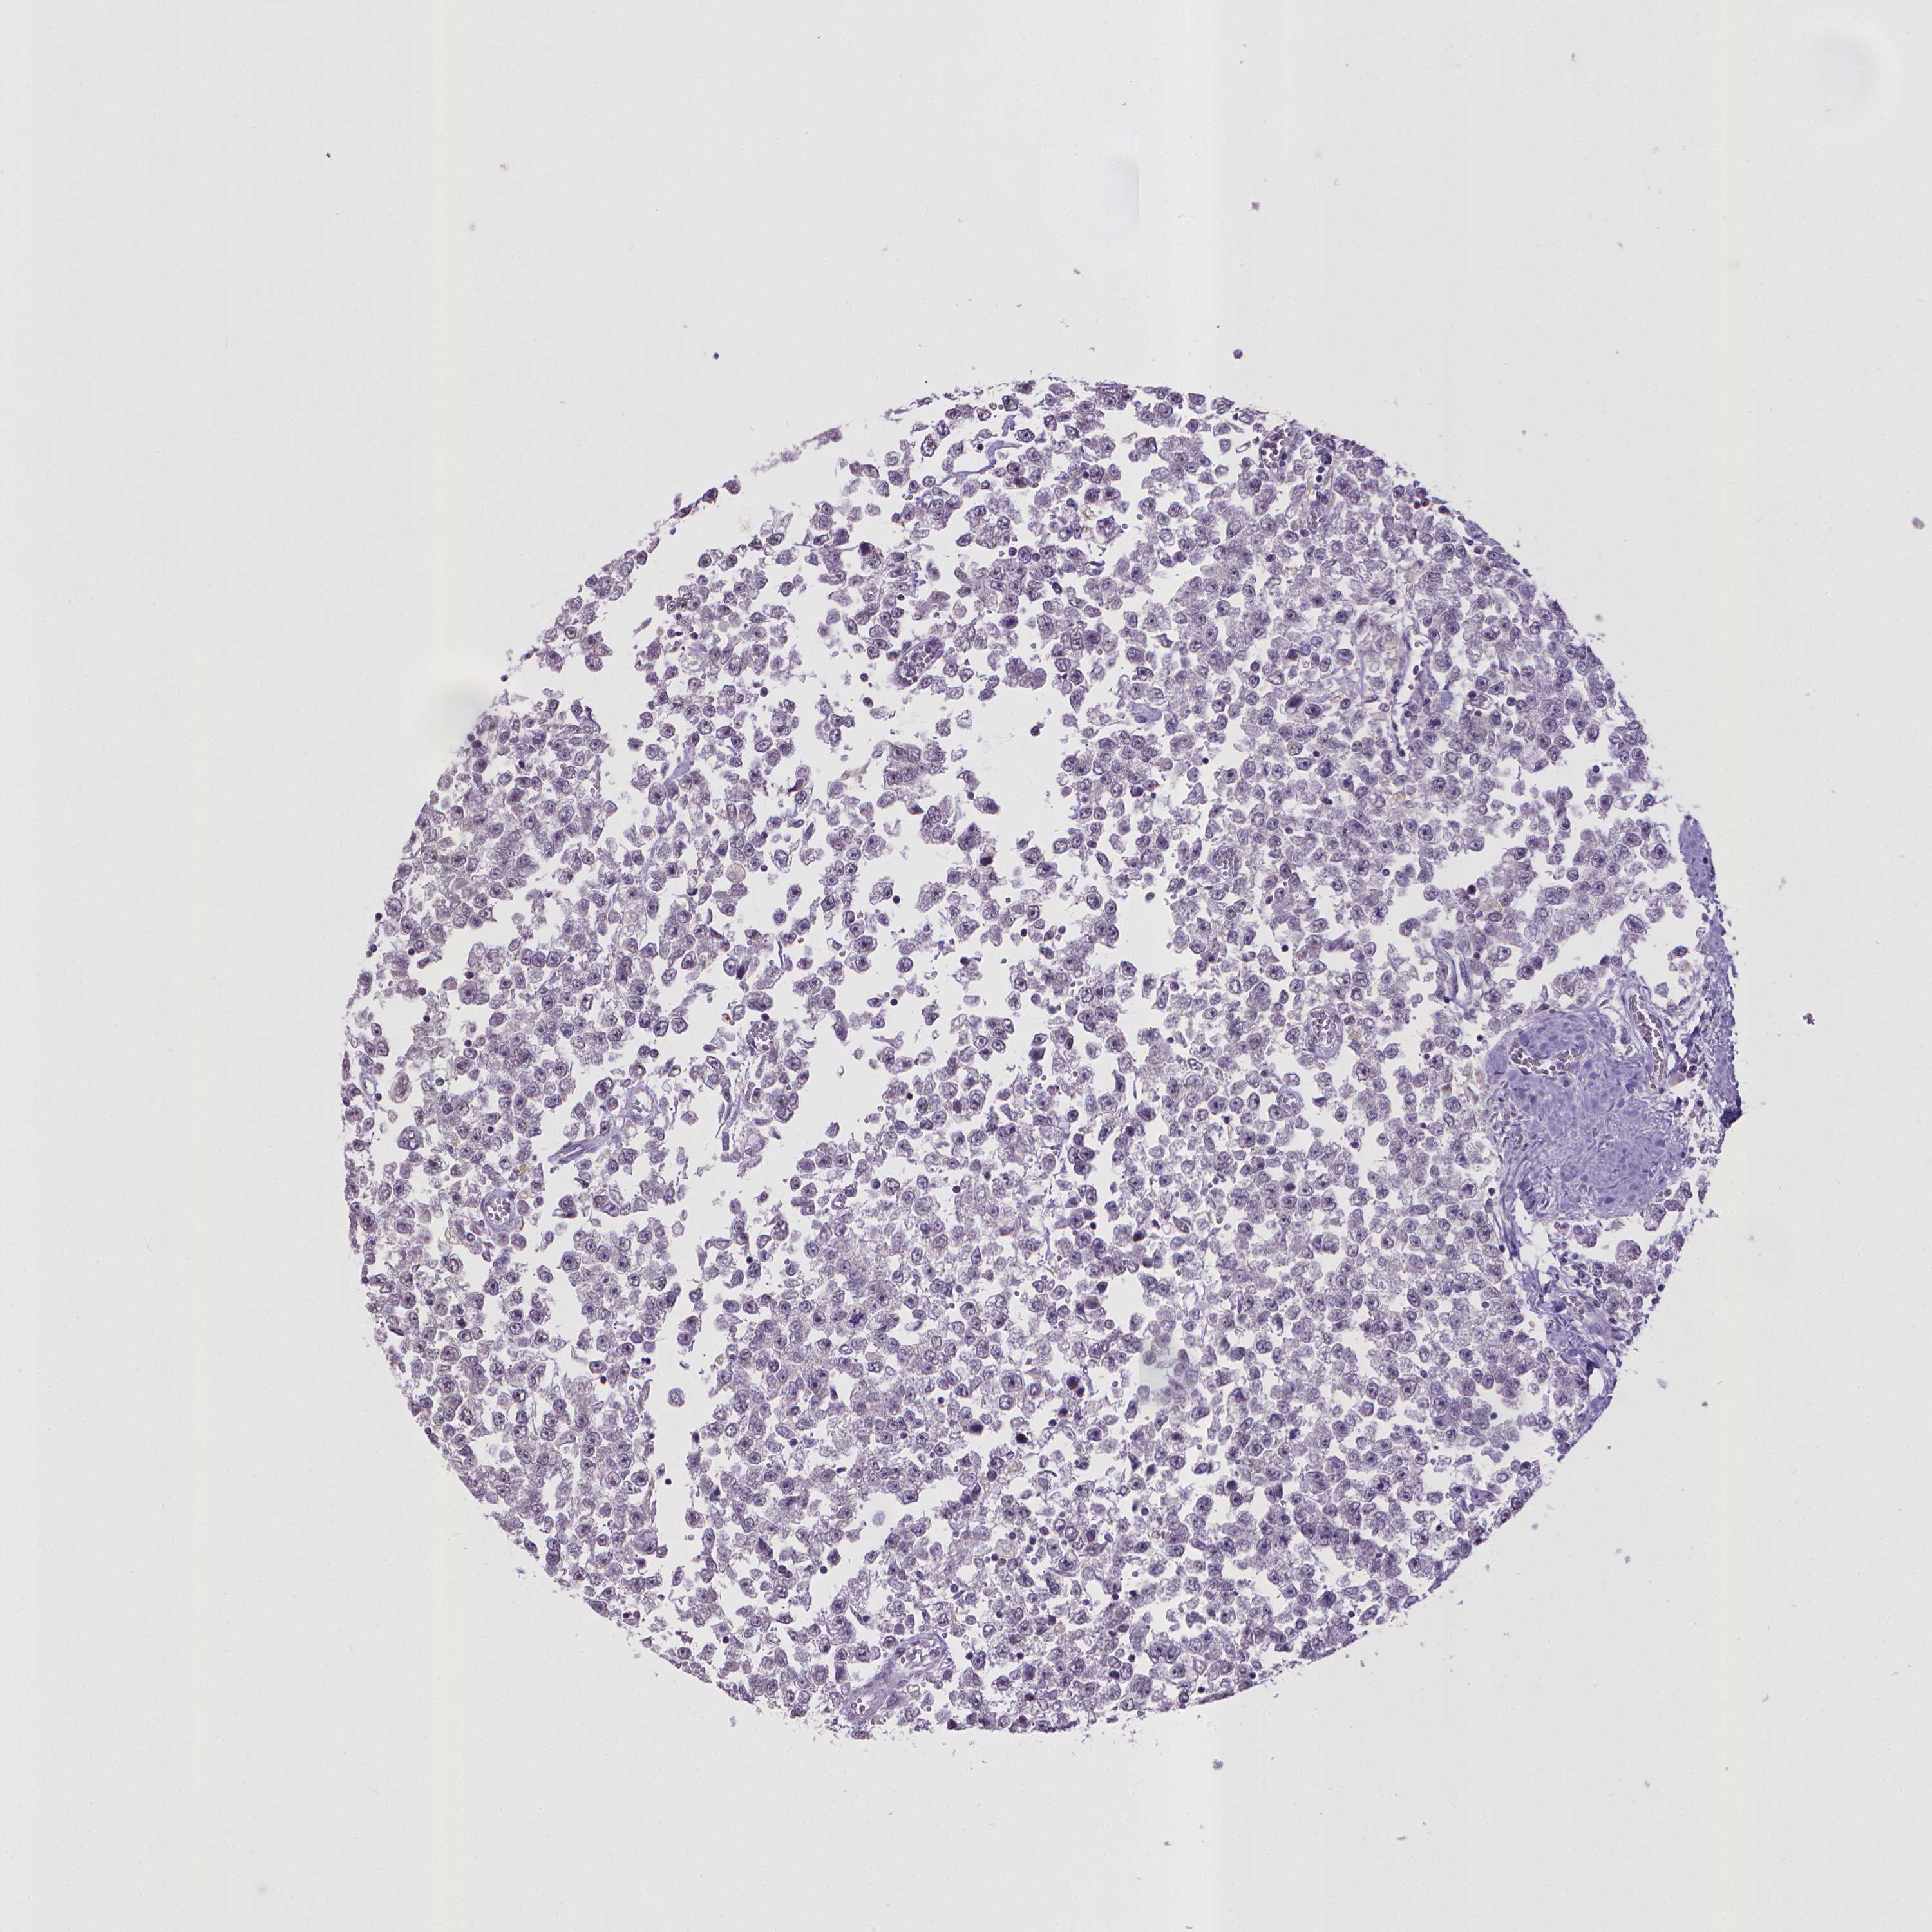

TESTIS CANCER - Protein expressioni

A mouse-over function shows sample information and annotation data. Click on an image to view it in a full screen mode. Samples can be filtered based on level of antibody staining by selecting one or several of the following categories: high, medium, low and not detected. The assay and annotation is described here.

Note that samples used for immunohistochemistry by the Human Protein Atlas do not correspond to samples in the TCGA dataset.

Antibody stainingi

Antibody staining in the annotated cell types in the current human tissue is reported as not detected, low, medium, or high, based on conventional immunohistochemistry profiling in selected tissues. This score is based on the combination of the staining intensity and fraction of stained cells.

Each image is clickable and will lead to virtual microscopy that enables deeper exploration of all samples and also displays staining intensity scores, fraction scores and subcellular localization as well as patient and tissue information for each sample.

Antibody HPA031115

Antibody HPA056942

Staining

High

Medium

Low

Not detected

Intensity

Strong

Moderate

Weak

Negative

Quantity

>75%

75%-25%

<25%

None

Location

Nuclear

Cytoplasmic/membranous

Cytoplasmic/membranous,nuclear

Seminoma, NOS

Carcinoma, Embryonal, NOS

Teratoma, malignant, NOS